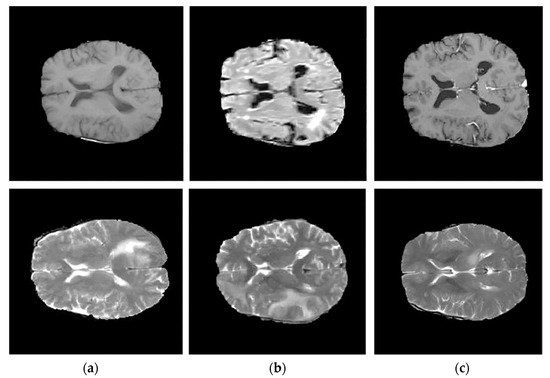

3.1. Step 1 Preprocessing Phase

- Groza, V.; Tuchinov, B.; Pavlovskiy, E.; Amelina, E.; Amelin, M.; Golushko, S.; Letyagin, A. Data preprocessing via multi-sequences MRI mixture to improve brain tumor segmentation. In Proceedings of the International Conference on Bioinformatics and Biomedical Engineering, Granada, Spain, 6–8 May 2020; Springer International Publishing: New York, NY, USA, 2020; pp. 695–704. [Google Scholar]